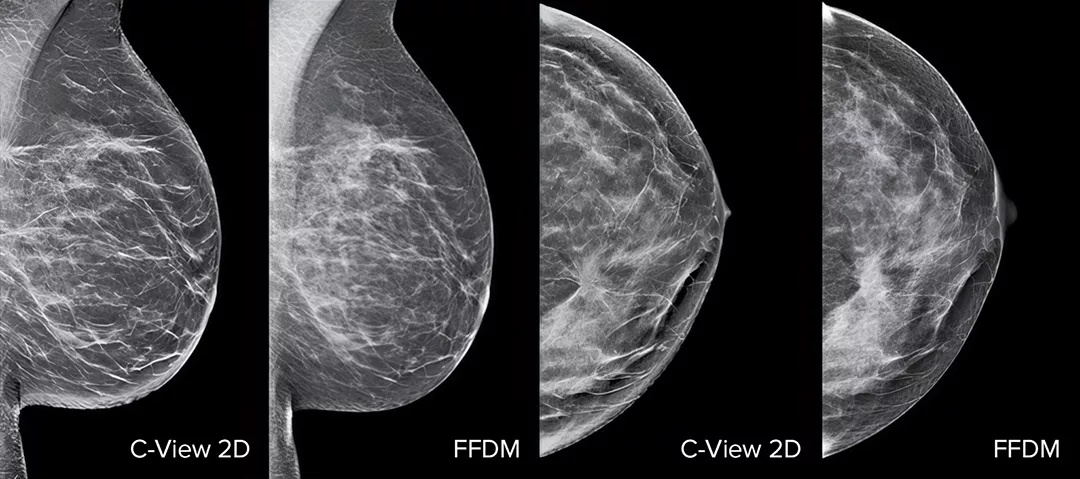

Raise your breast cancer screening performance1-4 with C-View software and instantly generated synthesised 2D images. It not only enhances details and speeds up the analysis, but also reduces radiation dose levels for your patients. C-View 2D images are clinically proven3,5 and FDA approved to diagnostically replace the FFDM images within a tomosynthesis screening exam.

Architectural distortions, mass lesions, and bright spots commonly found in microcalcifications are more visible in the C-View 2D image than on the traditional FFDM 2D images or tomo slices.4,6-9

C-View 2D images are clinically proven3,5 and FDA approved to diagnostically replace the FFDM images within a tomosynthesis screening exam. The images are also a navigational aid to the tomosynthesis slice review. Published studies show that the low dose 3D Mammography exam finds invasive cancer earlier, while also reducing false positive recall rates compared to 2D alone.4,5,7

Architectural distortions, mass lesions, and bright spots commonly found in microcalcifications, are more visible in the C-View 2D image than on the traditional FFDM 2D image or tomo slice.4,6-9